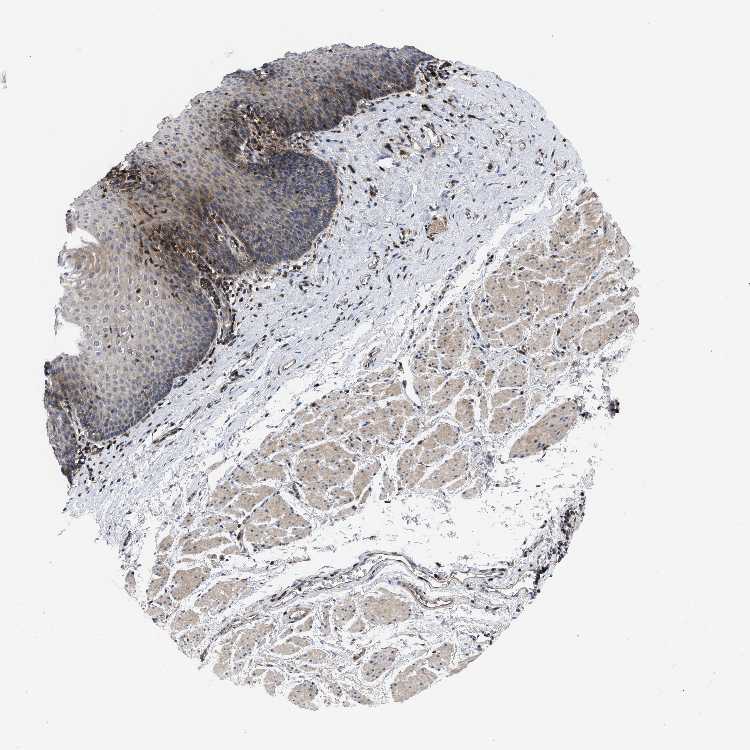

ESOPHAGUS - Antibody stainingi

Antibody staining in the annotated cell types in the current human tissue is reported as not detected, low, medium, or high, based on conventional immunohistochemistry profiling in selected tissues. This score is based on the combination of the staining intensity and fraction of stained cells.

Each image is clickable and will lead to virtual microscopy that enables deeper exploration of all samples and also displays staining intensity scores, fraction scores and subcellular localization as well as patient and tissue information for each sample.

Antibody HPA018162

Squamous epithelial cells Medium